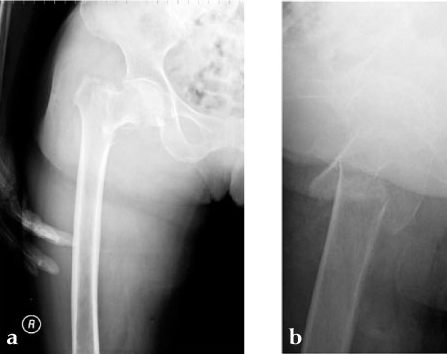

Case 3: 90-year-old male, injured by fall down.

Case provided by Toru Sato, Okayana, JP